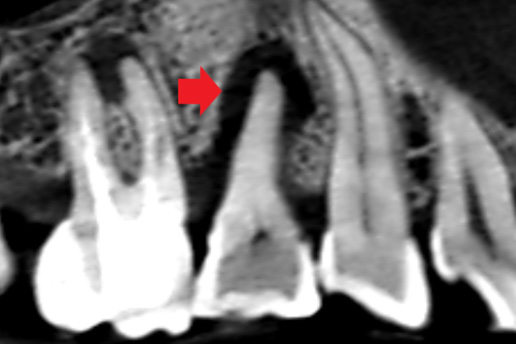

歯の根に膿がたまり他院で抜歯宣告をされた歯。最終的に抜歯せずに治療ができたケース。